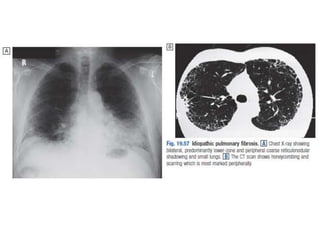

Pulmonary Fibrosis